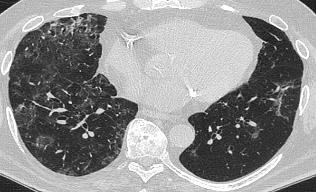

A 58-year-old female with recently diagnosed COVID-19 pneumonia was found to have a dry cough and dyspnoea in the setting of persistent bilateral hilar and mediastinal lymphadenopathy associated with bilateral nodular infiltrates. Of note, she immigrated to the USA from India 10 years prior, with the most recent travel to India 2 years ago. Quantiferon testing upon return to the USA was negative at that time. Workup included bronchoscopy with endobronchial ultrasound revealing non-caseating granulomas with negative stains for acid-fast bacilli (AFB). She was diagnosed with Stage 3 sarcoidosis and initiated on prolonged steroid taper with improvement of symptoms. With taper of steroid dose, however, she developed lymphocyte-predominant exudative effusion with negative cultures, and was reinitiated on a protracted steroid course with rapid symptom resolution. At 4-month follow-up, she had worsening CT findings upon steroid taper, and was started on azathioprine. One month later, she required hospital admission for worsening dyspnoea and fatigue. She was noted to be febrile, tachycardic, and tachypnoeic with worsening

hypoxia. Subsequent CT chest showed progression of bilateral nodular infiltrates with new right upper lobe consolidation and air bronchograms concerning for multifocal pneumonia (Figure 1). Incidentally, she was also noted to have calcified splenic granulomas. She developed rapid clinical deterioration, ultimately requiring mechanical ventilation, pressor support, and continuous renal replacement therapy. Repeat bronchoscopy revealed diffuse alveolar haemorrhage with multiple AFB smears positive for Mycobacterium tuberculosis. She was immediately initiated on quadruple therapy, but unfortunately, despite treatment, developed refractory shock and passed away 2 weeks after initial presentation.

A) Initial adenopathy with peripheral patchy ground glass opacities in the right lung following COVID-19 pneumonia. B) Persistent bulky adenopathy 1 year after initial presentation. C) Extensive nodularity throughout the right lung with increasing confluent opacities in the right upper lobe and stable mediastinal lymphadenopathy 2 years after initial presentation. D) Tuberculosis superimposed on sarcoidosis with progression of nodular infiltrates, worsening right upper lobe consolidation, and air bronchograms with incidental calcified splenic granulomas (not pictured).

Figure 1: CT progression of patient’s sarcoidosis and tuberculosis.